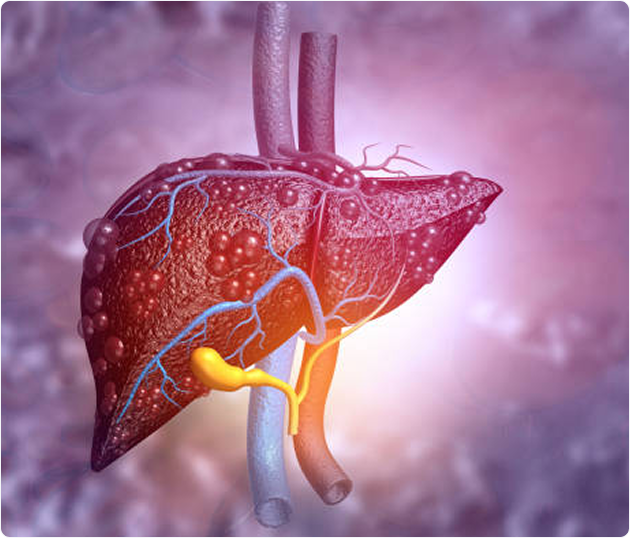

Un paciente con cirrosis hepática puede recibir diversos medicamentos que abordan tanto la enfermedad en sí como sus complicaciones, con el objetivo de mejorar los resultados clínicos y la calidad de vida.

A continuación, repasaremos los principales tratamientos farmacológicos que un paciente con cirrosis y/o alguna complicación puede recibir durante su enfermedad:

A continuación, repasaremos los principales tratamientos farmacológicos que un paciente con cirrosis y/o alguna complicación puede recibir durante su enfermedad:

Es la complicación más común de la cirrosis.

Son la primera línea de tratamiento para la prevención de la hemorragia variceal (tanto primaria como secundaria) y la reducción de la presión portal. Se debe considerar su uso para prevenir la descompensación en pacientes con hipertensión portal clínicamente significativa (HPC). El carvedilol es el BBNS preferido en la cirrosis compensada debido a su mayor eficacia en la reducción del gradiente de presión venosa hepática (GPVH) y su tendencia a un mayor beneficio en la prevención de la descompensación y una mejor tolerancia, así como la mejora de la supervivencia. Otro betabloqueador que puede utilizarse es el propranolol. Su médico monitorizará su frecuencia cardiaca durante su uso. Los BBNS deben reducirse o suspenderse temporalmente en caso de hipotensión progresiva o durante condiciones agudas como sepsis, PBE o IRA.

El uso de este debe fomentarse en pacientes con cirrosis y una indicación aprobada, ya que pueden disminuir la presión portal y mejorar la supervivencia. El fármaco más recomendado es la simvastatina. Sin embargo, en cirrosis avanzada, deben usarse a dosis más bajas y con seguimiento estrecho.